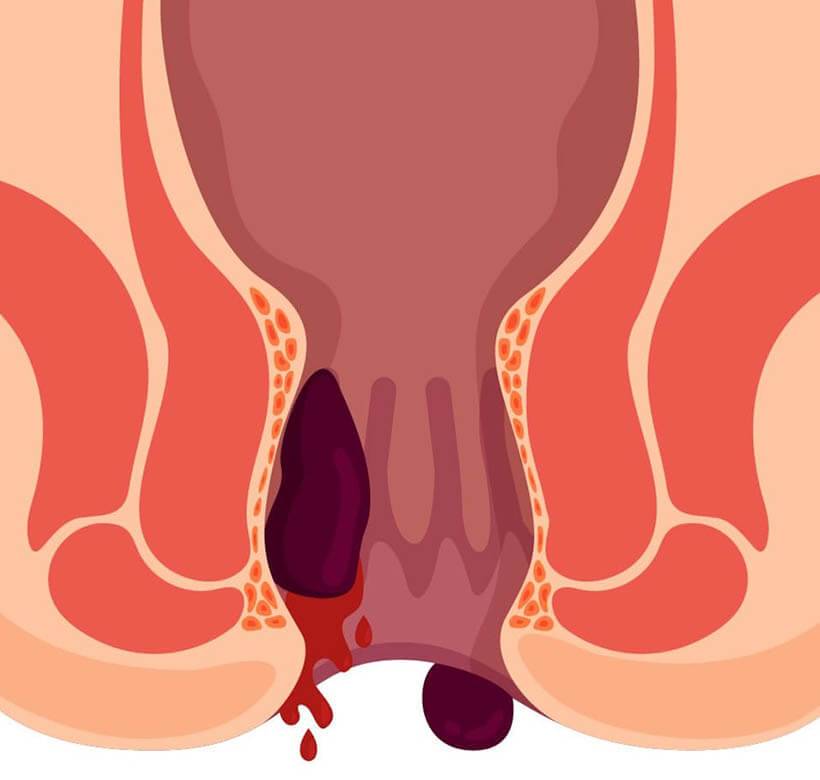

Dünyada en sık rastlanılan hastalıklardan biri olan hemoroid hastalığı, her dört kişiden birini etkiliyor. İlk belirtileri kanama ve ağrı olan hemoroidal hastalığın ana nedeninin sürekli ve aşırı ıkınma olduğunun altını çizen Anadolu Sağlık Merkezi Hastanesi Genel Cerrahi Uzmanı Prof. Dr. Vafi Atalay, “Bu hastalıkla özellikle günümüzde, tuvalete telefonla gitme alışkanlığı nedeniyle dışkılamaya konsantre olmayanlarda daha sık karşılaşılıyor” diye konuştu. Toplumda sanılanın aksine hemoroid bir hastalık değil herkeste bulunan anatomik bir yapı. Bu yapının iltihaplanması sonucu hemoroid şikayetlerinin oluştuğunu açıklayan Anadolu Sağlık Merkezi Hastanesi Genel Cerrahi Uzmanı Prof. Dr. Vafi Atalay, “Hemoroid dokusu, anüsün tam kapanmasını sağlayarak istemsiz gaz ve dışkı kaçışını önlemeye yardımcı olur. Bu damarsal yapıların şişerek sarkması ise hemoridal hastalıkları oluşturur. Halk arasında bu hastalıklara kısaca hemoroid ya da basur deniyor” şeklinde konuştu.

Rektal kanama, ağrı veya dışarıya sarkan doku gibi semptomların var2lığında vakit kaybetmeden bir sağlık merkezine başvurulması gerektiğini vurgulayan Prof. Dr. Vafi Atalay, Makattan gelen her kanamanın kaynağı hemoroid olmayabilir. Bu hastalık toplumda yaygın olarak bilindiği için çoğu kişi kanamanın nedeninin bu olduğunu düşünür ve doktora başvurmaya gerek duymaz. Kanamanın tümör veya başka bir bağırsak hastalığının da sinyali olabileceği unutulmamalı ve ciddiye alınmalı” şekilinde konuştu. Uzun süre hemoroid tedavisi alan genç hastalarda da tümör ile karşılaşabildiklerini ekleyen Prof. Dr. Vafi Atalay, “Kolorektal kanser dünyada en sık rastlanan türlerden biri, görülme sıklığı yükselirken rastlanma yaşı gittikçe düşüyor. Bu yüzden rektal kanama varsa mutlaka kolonoskopi yaptırılmalı” dedi.

Hemoroid Tedavi edilmezse anemiye yol açabilir

Hemoroidin ciddiye alınmadığı için tedavisine başlanılamadığı durumlarda bölgedeki kanamaya bağlı olarak ciddi bir anemi yani kansızlık gelişebileceğinin altını çizen Atalay, “Bunun sonucunda da ufak bir efor ile nefesinizin daralacağı kadar yorgun hissetmeye başlarsınız. Ten renginiz soluklaşır. Anemi özellikle ileri yaşlarda kalbi ekstra yorar ve hatta kalp yetmezliği bulguları ortaya çıkartabilir. İhmal edilen hemoroidler dışarı çıktıktan sonra ödemlenip yeniden içeriye giremeyebilir, makattaki şişlik de artacağı için bölgede kangrene ve ülserlere zemin hazırlanır. Bu gibi senaryolarda acil ameliyat şarttır, ani müdahalelere mecbur kalmadan yani hastalığın ilerlemesini beklemeden bir sağlık merkezine başvurmak çok önemli” şeklinde konuştu. (BSHA – Bilim ve Sağlık Haber Ajansı)